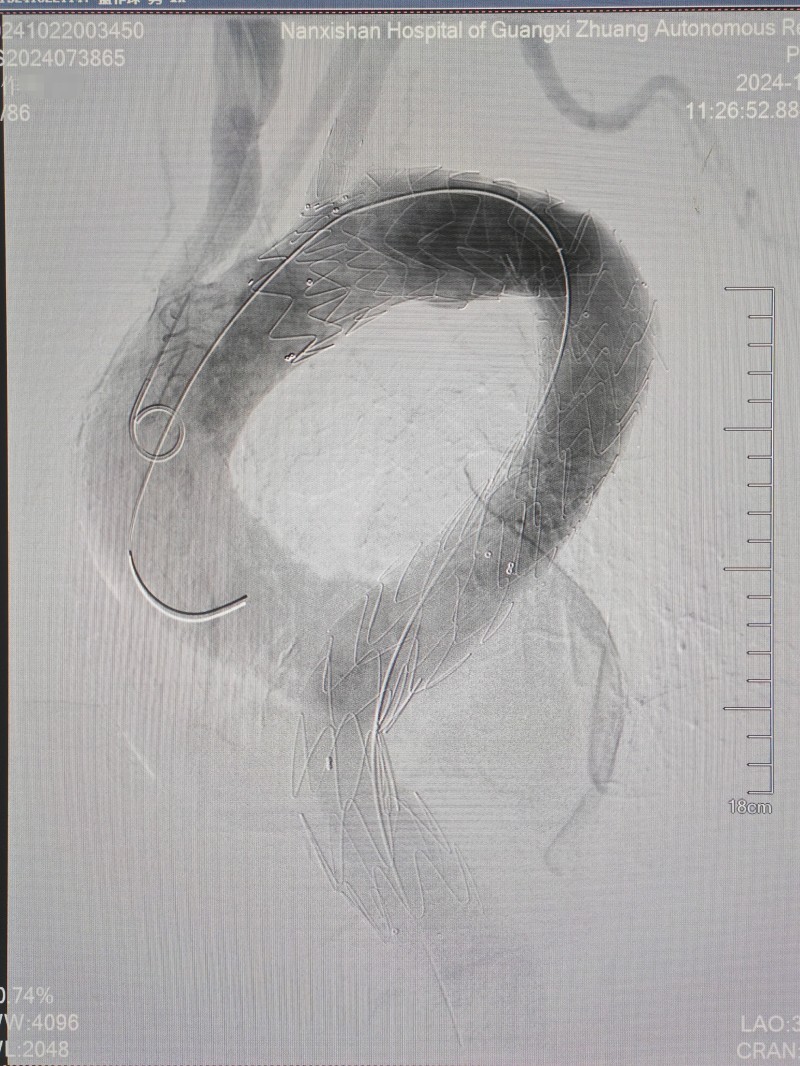

首先,医生们为患者进行了全麻下分支型胸主动脉覆膜支架腔内隔绝术。由于动脉瘤瘤体直径较大且累及范围较长,一个分支型覆膜支架无法完全覆盖瘤腔,于是在远端又接入了一个直筒支架。复查造影显示动脉瘤隔绝良好、无内漏,手术效果达到预期,“排雷”成功!

图片5:胸主动脉支架植入术后